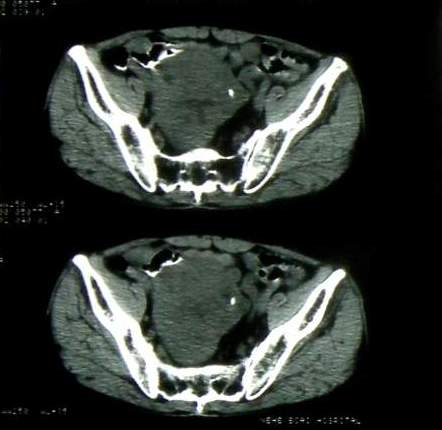

男 60岁,下腹部肿块半年余

前列腺肥大,密度不均。伴盆腔实性肿块。考虑前列腺癌伴盆腔转移。建议增强扫描。

考虑来源于肠道的肿瘤,乙状结肠?询问排便情况

盆腔恶性占位,间质瘤可能性大

乙状结肠间质瘤

病理结果:肠系膜肉瘤